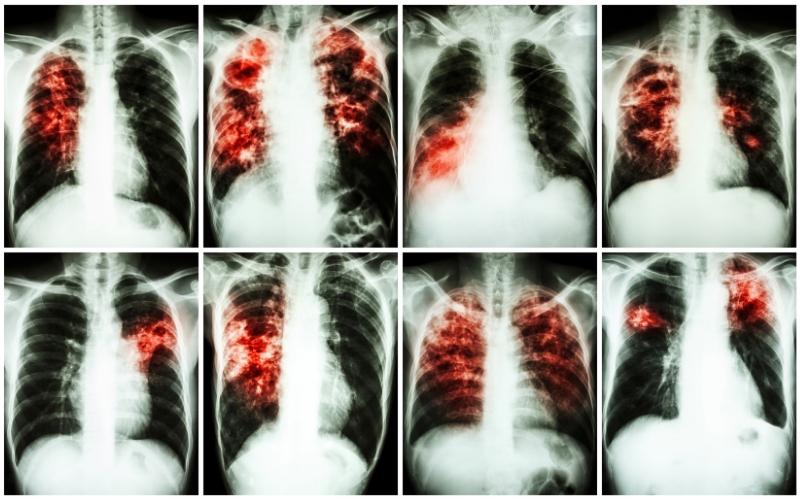

Ho khan, ho từ ít đến nhiều nhưng bệnh nhân thường không để ý mình bị ho từ khi nào. Trường hợp ho khan kéo dài và sốt nhẹ trên 3 tuần, đặc biệt là sốt về chiều thì cần chụp X-quang phổi và xét nghiệm đờm để tìm trực khuẩn lao.

Ngoài 2 xét nghiệm trên, bệnh nhân có thể thực hiện một số xét nghiệm bổ sung khác như: nhuộm soi tiêu bản đờm, nuôi cấy vi khuẩn lao trong phòng thí nghiệm, chụp X - quang phổi,...